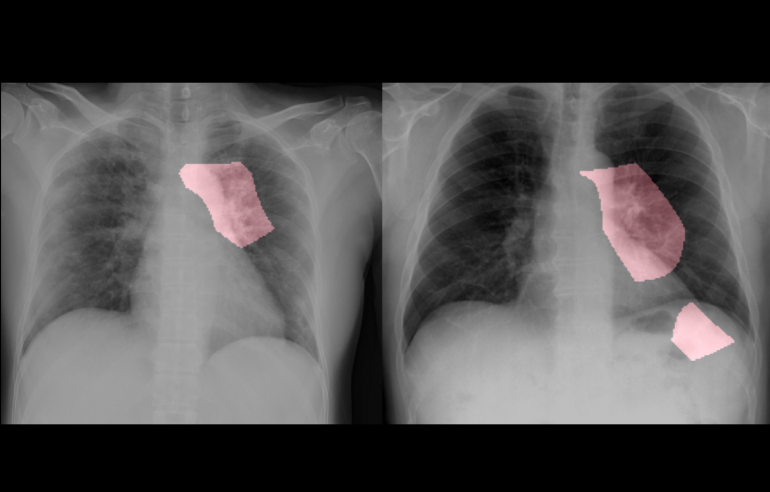

The tool, called COVID-Net, was created in collaboration with the University of Waterloo’s Vision and Image Processing (VIP) Lab. An important step in the fight against COVID-19 is the effective screening of infected patients, with one of the key screening approaches being radiological imaging using chest radiography.

DarwinAI’s tool is aimed to accelerate the development of highly accurate and practical deep learning solutions for detecting COVID-19 cases, in a way that is open and accessible to the public. DarwinAI’s dataset includes 5,941 chest radiography images across 2,839 patient cases. The startup is open-sourcing this model so the ecosystem can create a tool to assist health care professionals in combating the pandemic.

DarwinAI and the VIP Lab are also launching an explainability tool that shows how their AI technology reaches its COVID-19 detection decisions. The organizations are asking researchers or clinicians that would like access to the explainability tool to assist, or have COVID-19 data to share, to contact DarwinAI.

Image source DarwinAI